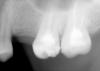

ДД! Сняла старую м/к коронки на 21, планирую поставить циркониевую, сейчас стоит временная. После снятия обнаружились остатки старого штифта. Врач предлагает удалит штифт, поставить правильно, поглубже СВШ и композит или вкладку метал. Вкладки ЗПС у нас не делают. Что посоветуете?

И посмотрите ОПГ, пожалуйста,где еще нужно перелечить каналы?

post-10065-1305780317_thumb.jpgpost-10065-1305780330_thumb.jpgpost-10065-1305780349_thumb.jpg